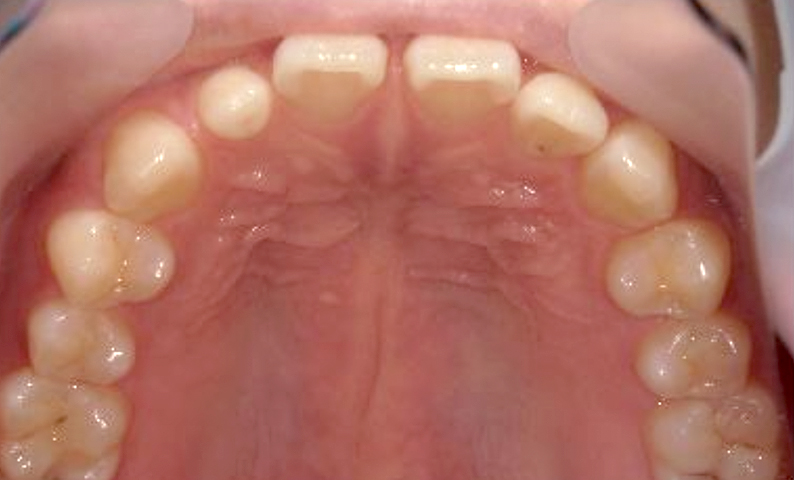

| 治療前 | 治療後 |

|---|---|

|